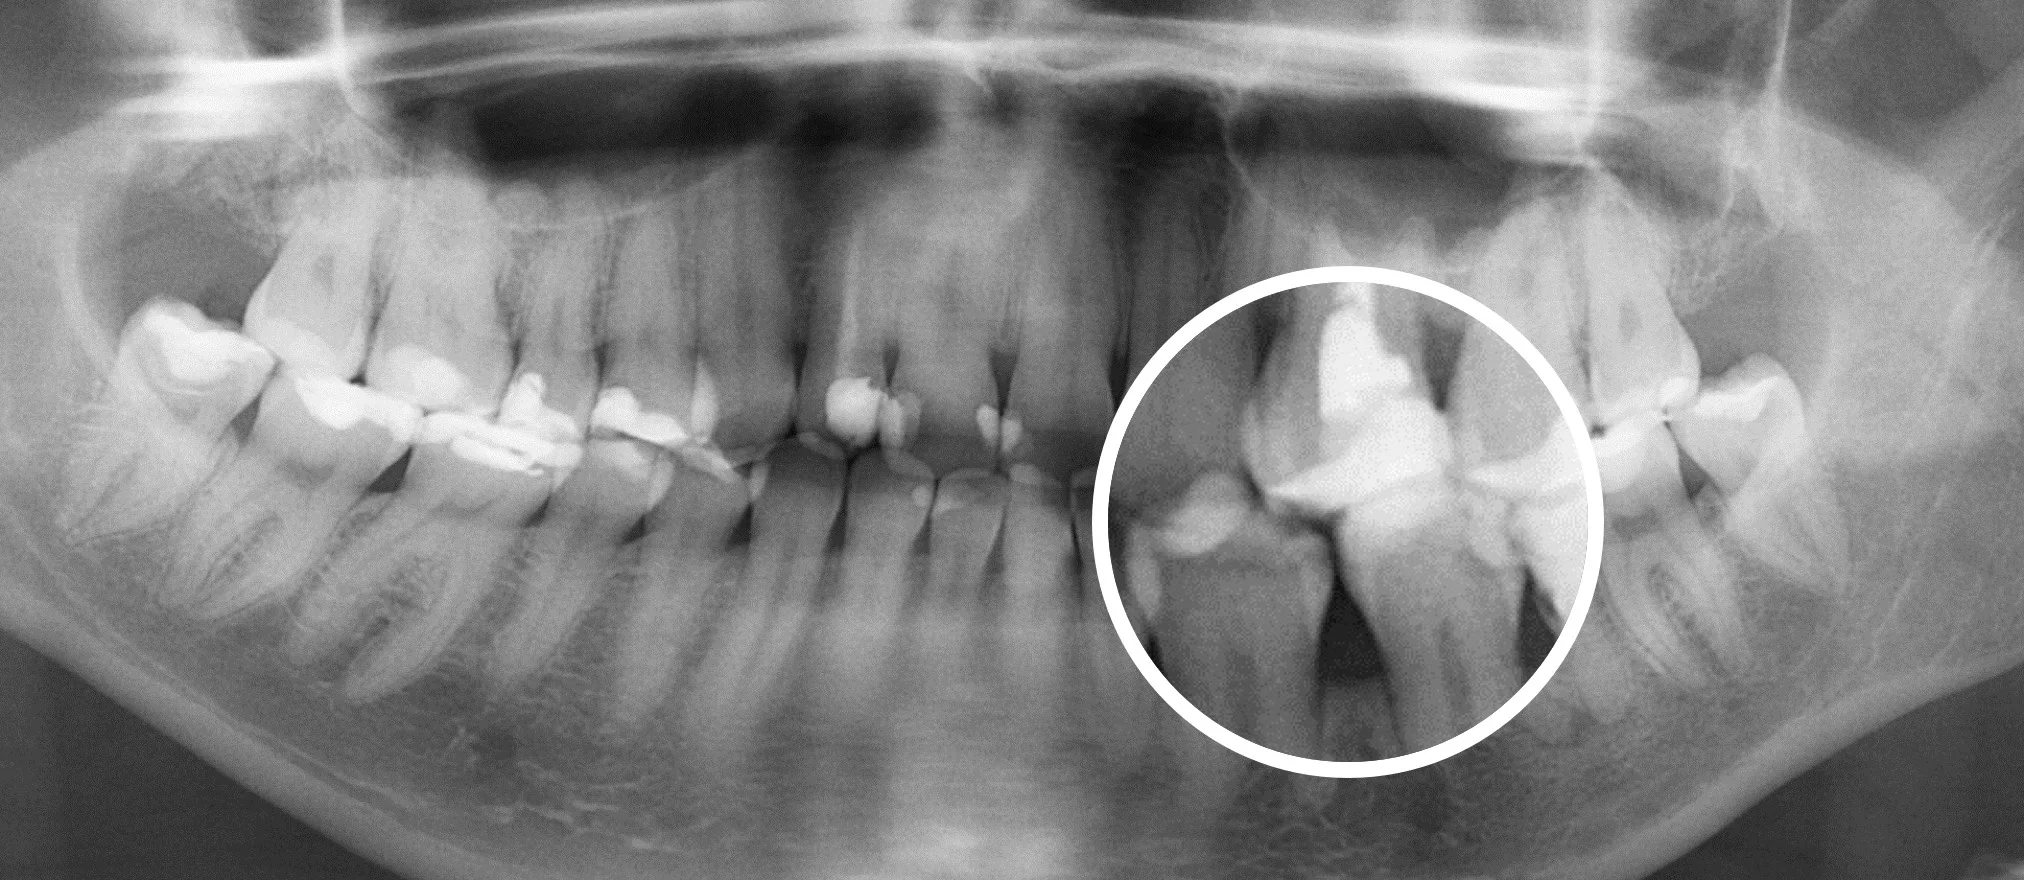

Стоматологическая нейросеть оценивает КТ и сверяет с информацией в своей обширной базе данных. Так она находит скрытые формы кариеса, периодонтиты и другие заболевания костной ткани, кисты, гранулемы и опухоли. Даже участки с минимальным подозрением отмечаются, чтобы ими занялся стоматолог.

- Загрузка результатов в ИИ. Отправляем ваши снимки в Diagnocat, который за 7 минут проверяет их по множеству параметров. В результате стоматолог получает визуализацию и презентацию всех обнаруженных проблем. Нейросеть подсвечивает, приближает и поясняет про состояние проблемных единиц.

- Подготовка плана лечения. Стоматолог подробно изучает отчет, сопоставляет его с вашими жалобами и предлагает варианты лечения. Раннее обнаружение в большинстве случаев помогает ограничиться консервативной терапией и сохранить зуб даже без хирургических вмешательств. Помните, мы не доверяем ИИ постановку диагноза – он только подсвечивает зоны риска. Окончательное решение всегда за опытным врачом.